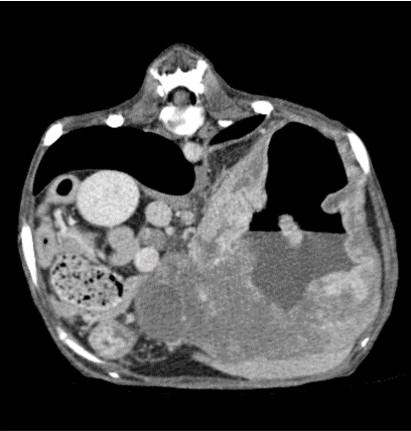

CT 검사

CT는 신체의 여러 각도에서 x-선을 투과시킨 후 단면 영상과 3차원적 입체영상을 얻을 수 있어 해부학적 구조와 병적 변화 정도를 정확하고 빠르게 평가할 수 있습니다.

CT 검사는 각종 종양과 염증, 외상 및 신체 기형과 같은 질환의 진단에 유용하게 사용될 수 있으며 수술이 지시되는 경우에도 진단을 넘어 정확한 해부학적 구조의 평가가 가능해져 이를 통해 수술 계획을 수립할 수 있습니다.

건국대학교 동물암센터에서 보유하고 있는 CT는 여러 개의 디텍터를 갖고 있는 multi-detector CT (MDCT)로써 촬영 시간 및 피폭량을 최소화 할 수 있는 장점이 있습니다. 여러 개의 디텍터를 통해 선명한 영상을 빠르게 구현해 냄으로써 진단의 정확성을 높일 수 있습니다.

대표질환

- 종양 진단 (두경부, 흉강, 복강, 사지 골격) 및 전이 평가

- 골격계 질환 및 골절 합병증 평가

- 혈관 기형 (PDA, PSS, vascular ring anomaly 등)

- 척추 질환 (척추 골절, hemivertebra)

- 폐 질환

위 종양 -

견갑골 종양 -

기흉 -

전신문맥단락(PSS)